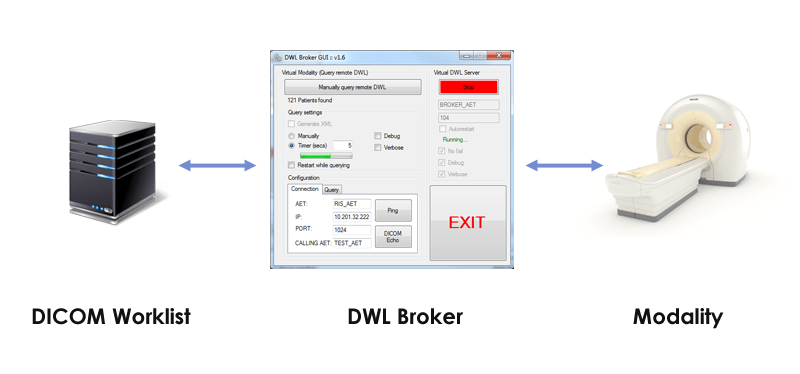

Лазерная камера для печати медицинских изображений на пленке стандарт dicom